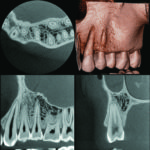

Dental Arc FOV (R 100 x H 80mm)